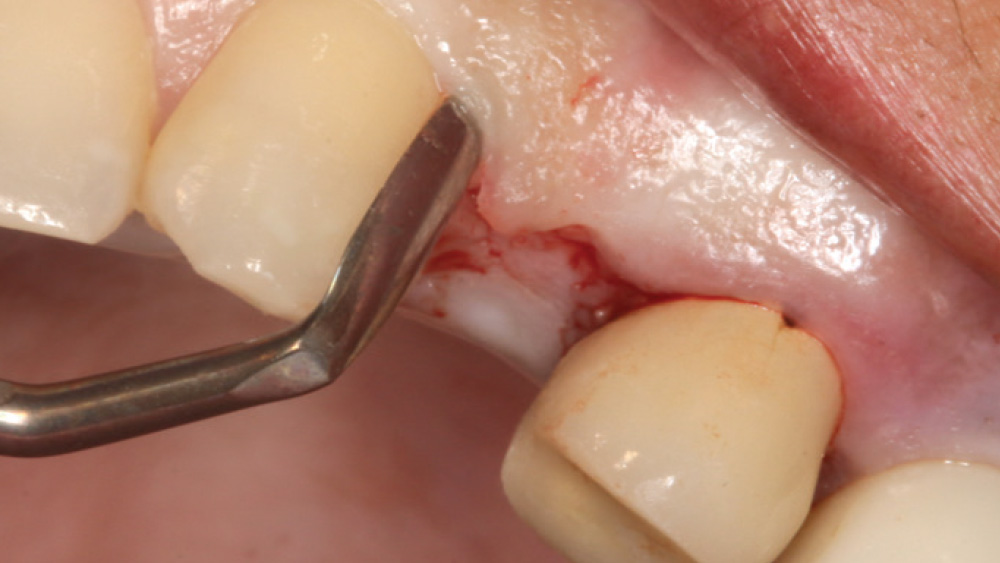

In contrast, with a flapless procedure, a tissue punch is used to gain access to the bone through the gingiva, minimizing postoperative discomfort by eliminating incisions in the mucosal tissue. Whenever mucosal tissue is incised, prostaglandin and histamine are released, resulting in potential postoperative swelling and pain. Therefore, when there is an adequate width of attached gingiva on the facial aspect of an implant site, a flapless procedure may be indicated, eliminating any suturing requirements.

CASE REPORT

The following case, which I performed alongside Dr. Stephanie Tilley of Pensacola, Florida, illustrates the use of both surgical techniques for the same patient, who presented with edentulous spaces in the areas of both right and left maxillary first bicuspids. Due to varying soft-tissue volume on each side of the arch, implant surgery was performed using a flapless procedure for one site, while the attached gingiva was reflected to expose the available hard tissue for the other. As a result of proper site evaluation, treatment planning and restorative-driven implant placement, both surgical techniques led to successful outcomes for the patient.